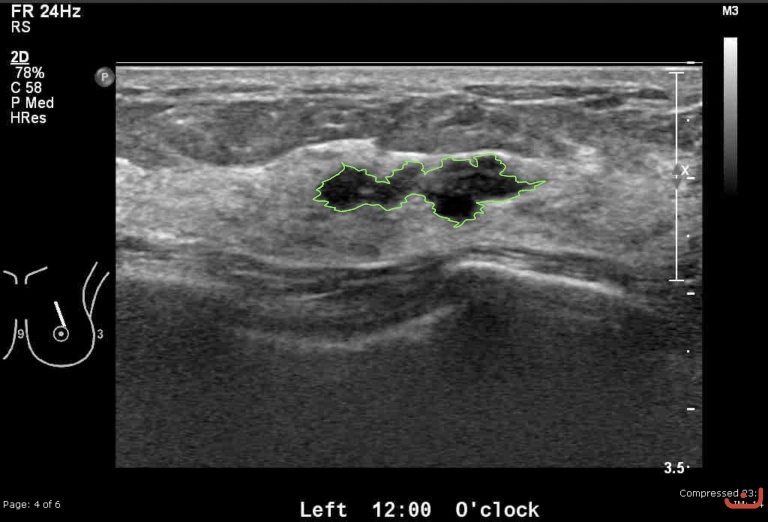

Case 28-G1

Malignant solid mass

Friday, 22 May 2015

183.92 KB (768 x 522 px)